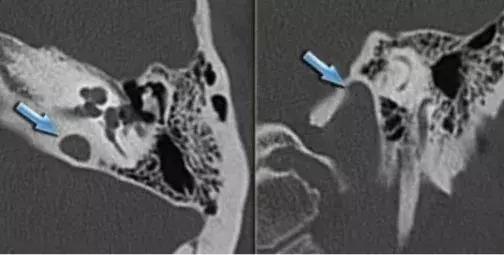

解剖变异的患者大多数没有临床症状,最常见为听力下降和搏动性耳鸣,其次是眩晕和出血。

除了以上这三种颈内动脉异位、颈内动脉外位、颈静脉球高位以外,还有乳突导血管异常、上半规管骨裂和后半规管骨裂。